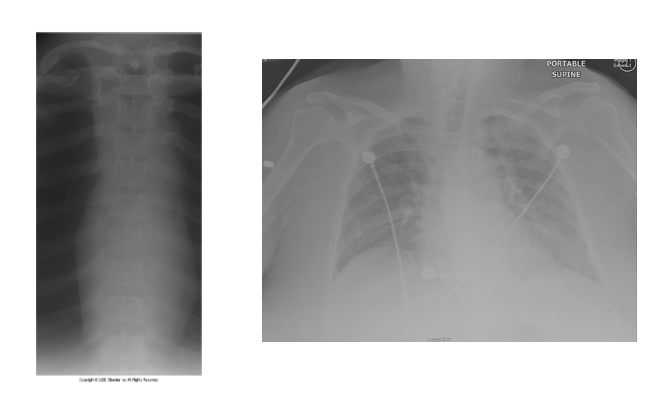

What is wrong with this xray images

This image shows scatter and fog and how little contrast there in the image